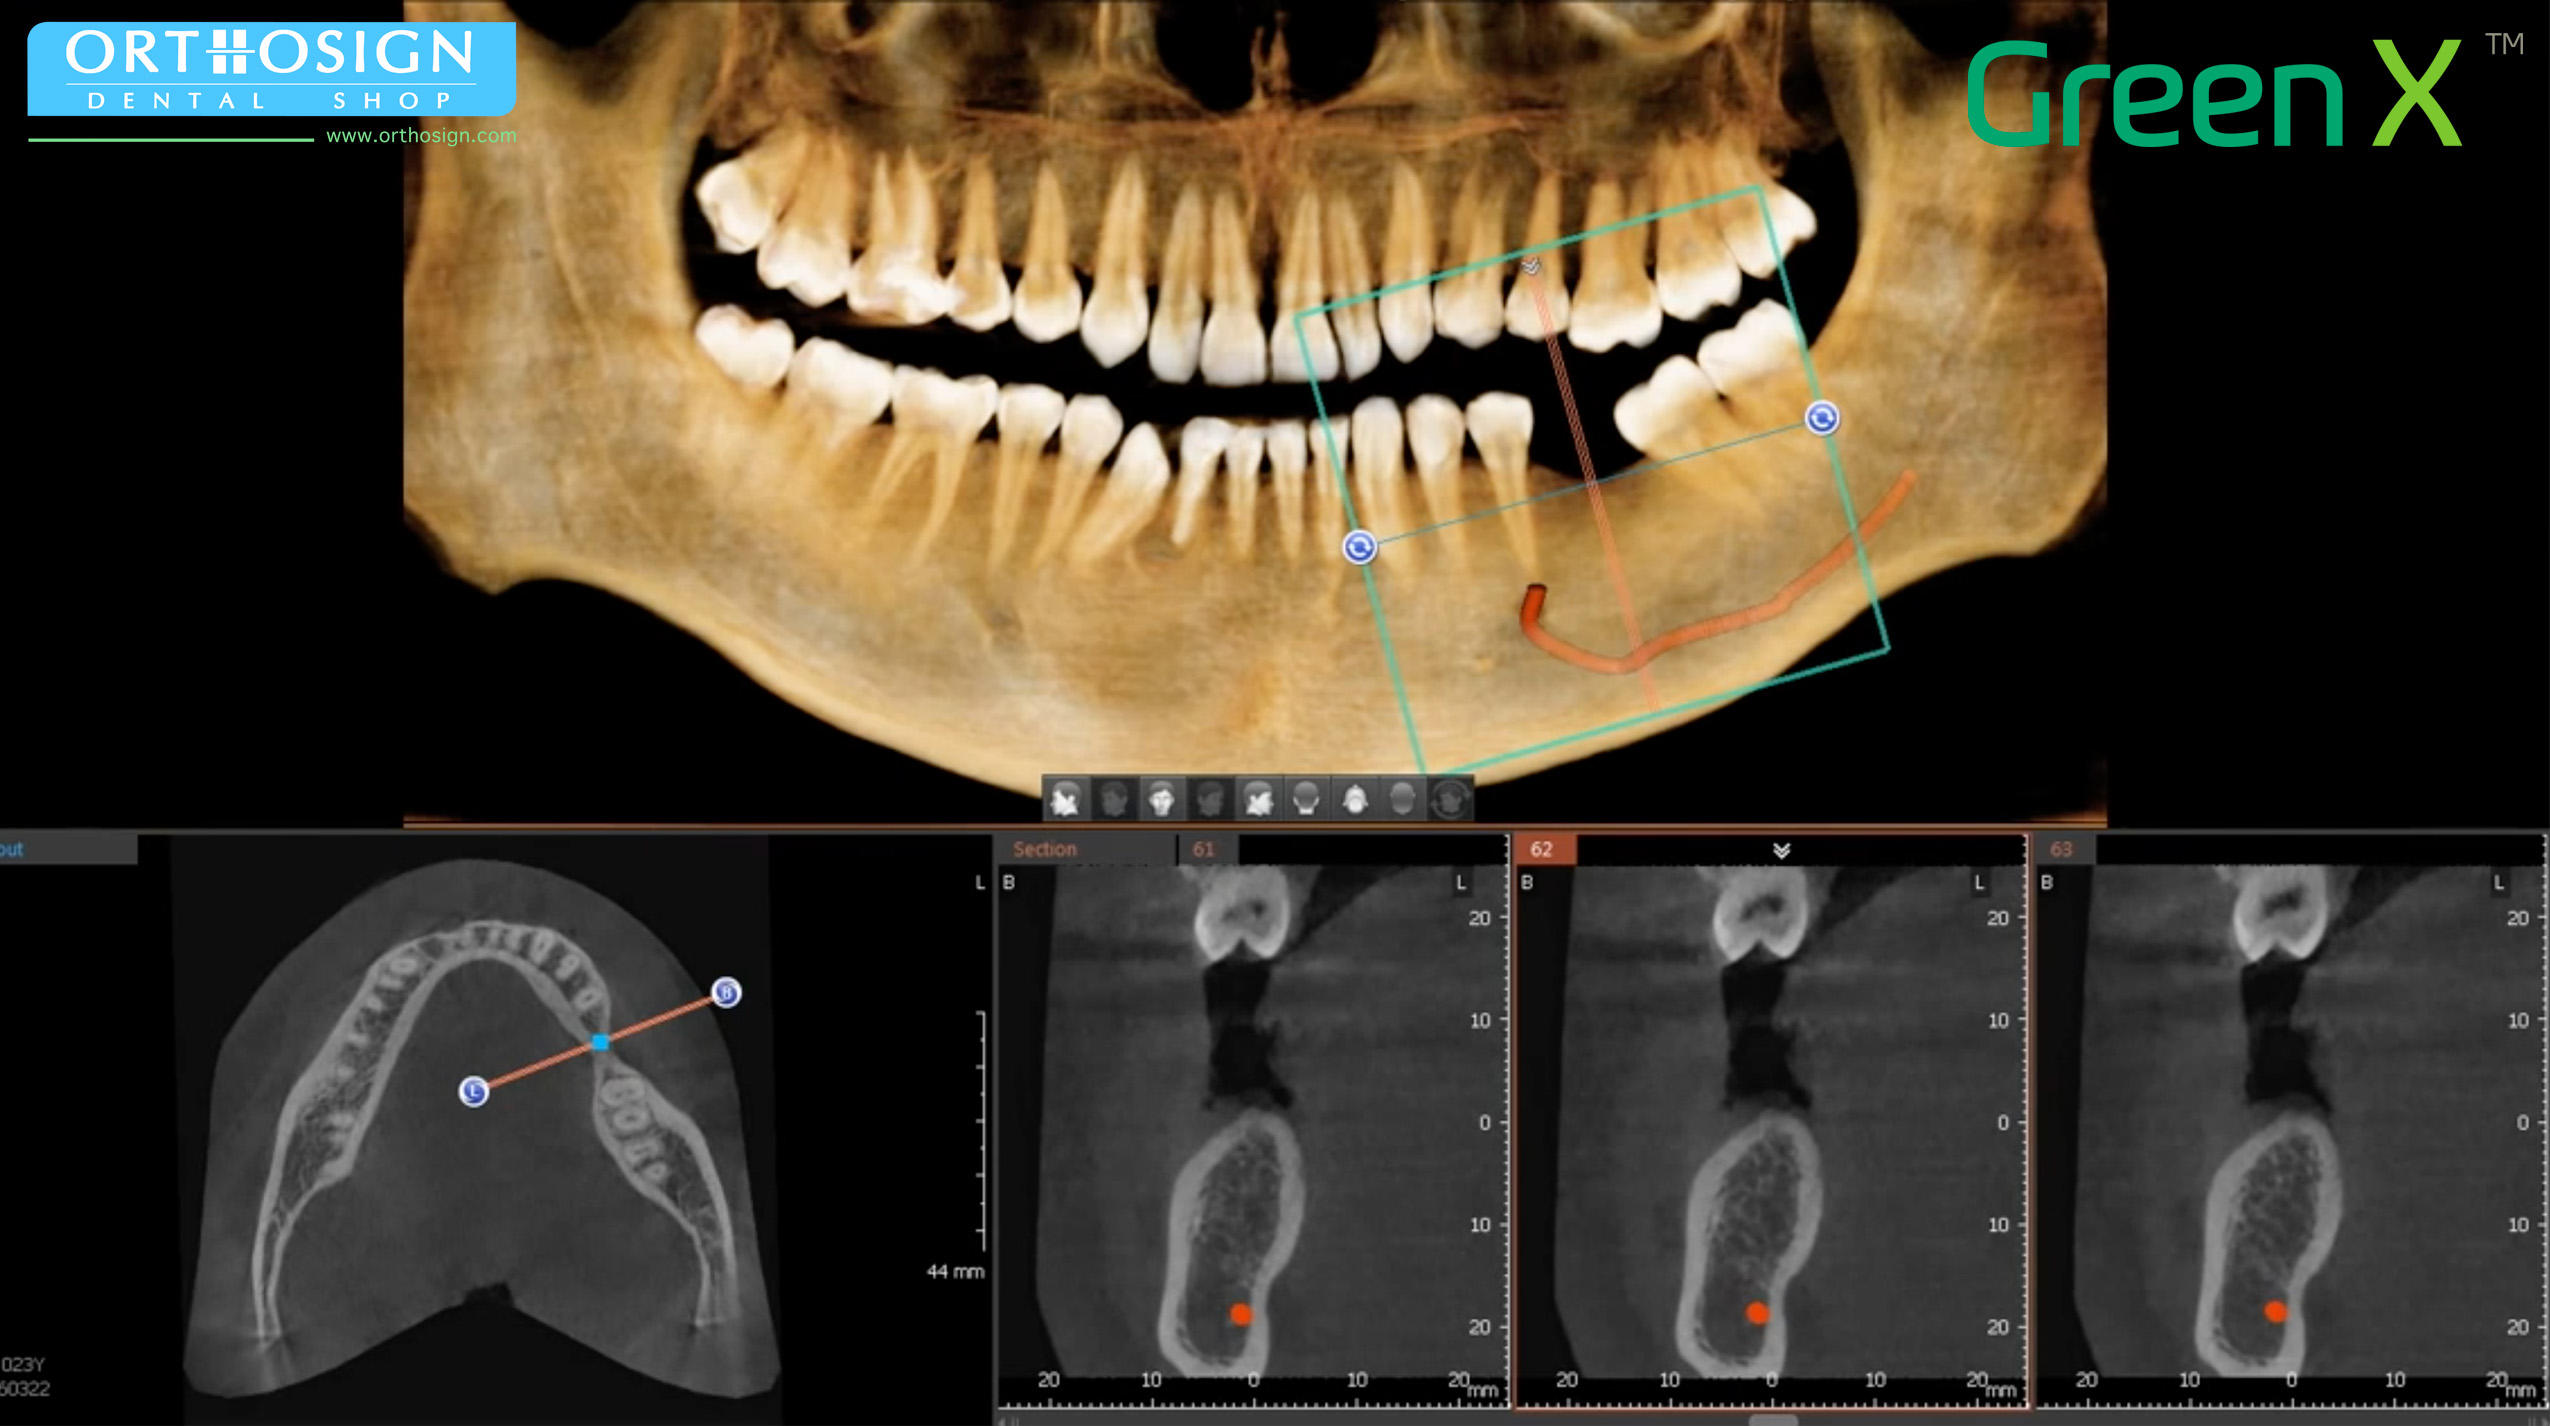

- CBCT, Cone Beam Computer Tomography. Imágenes en 3D de 18 x 24 cm.

- FOV hasta 24 x 15 cm (Double Scan). Sensor 18 x 15 cm.

- Modo ENDO con alta resolución 4 x 4 cm (Voxel de 0.05 mm.).

- Radiografía Panorámica (ortopantomografía).